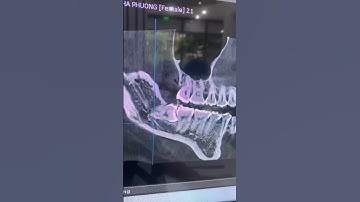

Cận cảnh Nhổ răng khôn có chân răng sát ống dây thần kinh hàm dưới